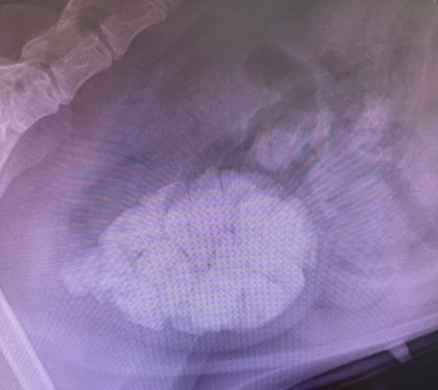

Diagnostic Imaging Results

X-ray examination showed a large number of mineralized opacities within the bladder, consistent with the radiographic appearance of multiple bladder stones. When stones are numerous or large, they can not only cause continuous irritation to the bladder wall but may also move into the urethra with urine flow, increasing the risk of urethral obstruction. Therefore, diagnostic imaging is of significant value for cases with persistent hematuria or recurrent urinary symptoms.

Figure 2 | X-ray image showing a large number of mineralized opacities in the bladder, consistent with multiple bladder stones.